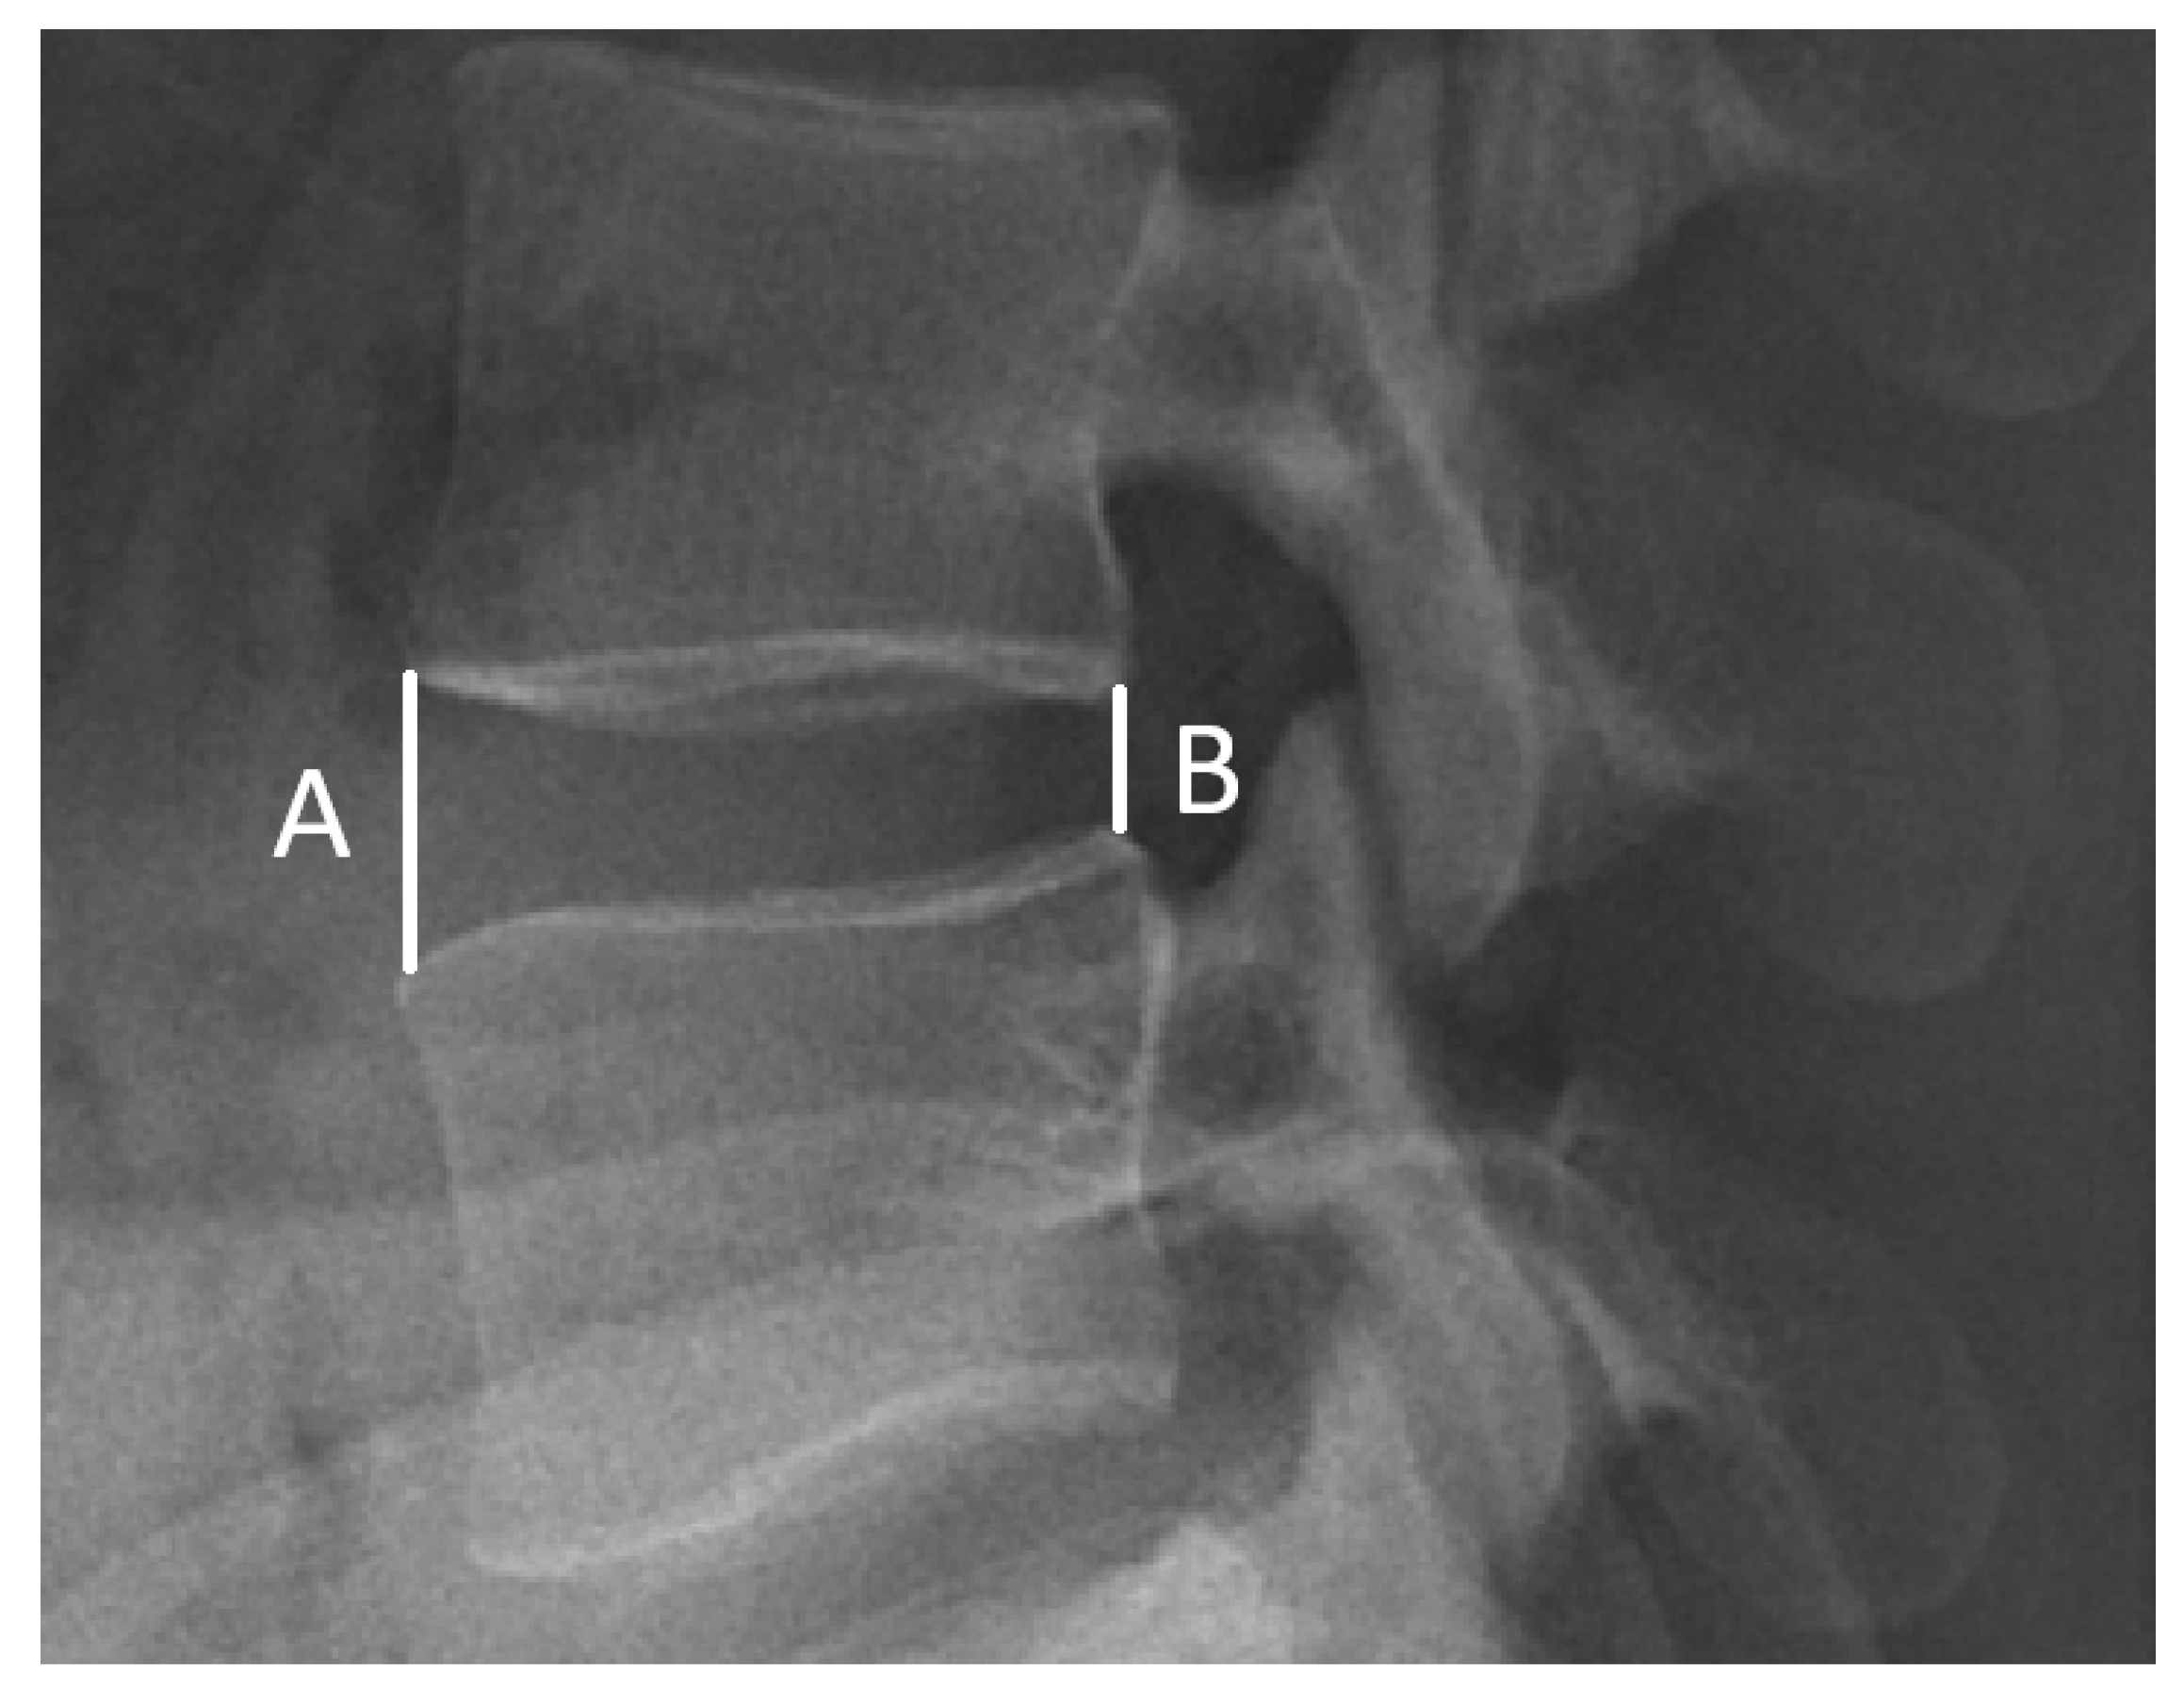

Thirdly, a radiographic assessment was conducted. For all cases studied, a lateral upright lumbar radiograph was obtained before and 6 months after the operations. To evaluate disc differences, the intervertebral disc height (IDH) was calculated preoperatively/postoperatively using Dabbs’ method [34,35]. The IDH was recorded as the average sum at the height of the anterior (A) and posterior (B) edge of the disc. The calculated formula was ((A + B)/2) (Figure 1). Average IDH values were compared among the three groups. Furthermore, the correlation between the clinical outcomes and changes in postoperative IDH was evaluated. All of the imaging calculations were performed by the same radiologist.

Figure 1.

Measurement of disc height. Calculation of disc height via Dabbs’ method (A + B/2).